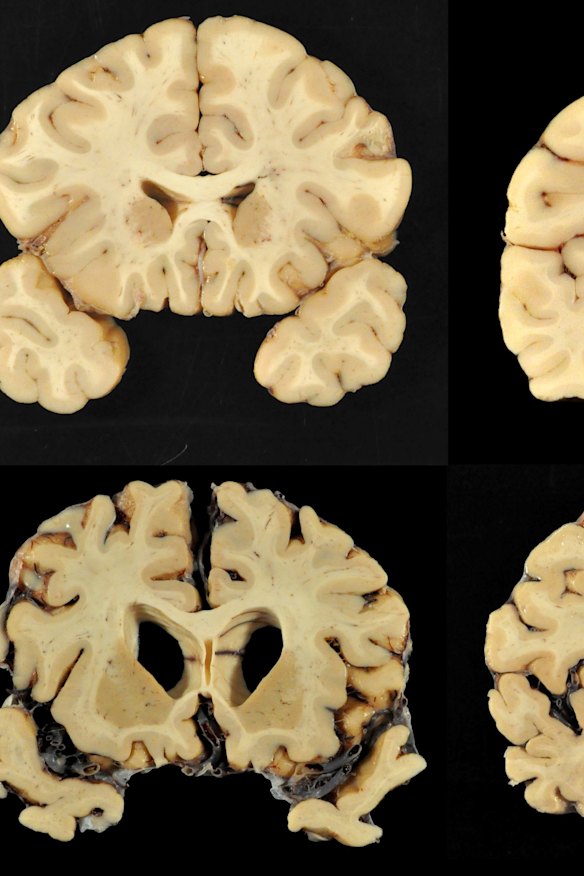

This combination of photos provided by Boston University shows sections from a normal brain, top, and from the brain of former University of Texas football player Greg Ploetz.Ann McKee, MD

Of the 202 players, 111 of them played in the NFL - and 110 of those were found to have chronic traumatic encephalopathy, or CTE, the degenerative disease believed to be caused by repeated blows to the head.

In addition to the 111 brains from those who played in the NFL, researchers also examined brains from the Canadian Football League, semi-professional players, college players and high school players. Of the 202 brains studied, 87 percent were found to have CTE. The study found that the high school players had mild cases, while college and professional players showed more severe effects. But even those with mild cases exhibited cognitive, mood and behavioral symptoms.